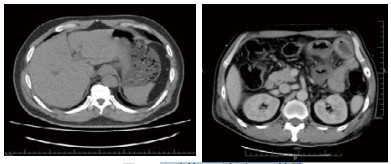

入院后在中心静脉压、有创动脉血压、每小时尿量、血气分析等严密监测下扩容补液、纠正酸中毒、亚胺培南西司他丁钠针联合利奈唑胺针抗感染、持续性血液净化纠正内环境等综合治疗后,病情逐渐好转,尿量增加,酸中毒纠正,肾功能恢复,血钠、血酮体降至正常,血糖控制在10 mmol/L以下。入院后第2天发现患者右上肢肢端温度低,右拇指发黑,血管超声示右上肢肱动脉远心端管腔闭塞,食道超声提示主动脉瓣近无冠瓣基底部可见4 mm×4 mm中等回声。入院第3天复查CT示肠系膜上静脉及门静脉积气消失(图 2)。入院第4天血培养回报:左侧外周为产气肠杆菌,右侧外周为草绿色链球菌,根据药敏结果调整抗菌药物为头孢曲松针联合左氧氟沙星针治疗,患者病情逐渐好转后出院。

| 图 2 入院第3天复查CT结果 |

本例患者出现肠系膜上静脉及门静脉远端积气,考虑系糖尿病酮症酸中毒、高渗性昏迷合并感染性心内膜炎,心脏感染性栓子脱落引起肠系膜动脉栓塞,导致肠道缺血损伤继发肠道产气肠杆菌感染,大量气体产生进入肠系膜上静脉及门静脉系统;或者肠道缺血损伤,肠壁通透性增高,肠道内产气细菌经血流进入门静脉系统,在局部繁殖产气引起。其腹部CT提示十二指肠水平部、升部及上段空肠局部肠壁肿胀,符合肠道缺血性改变,但后续治疗过程未见明显肠道坏死表现,故只行抗感染等保守治疗[7]。